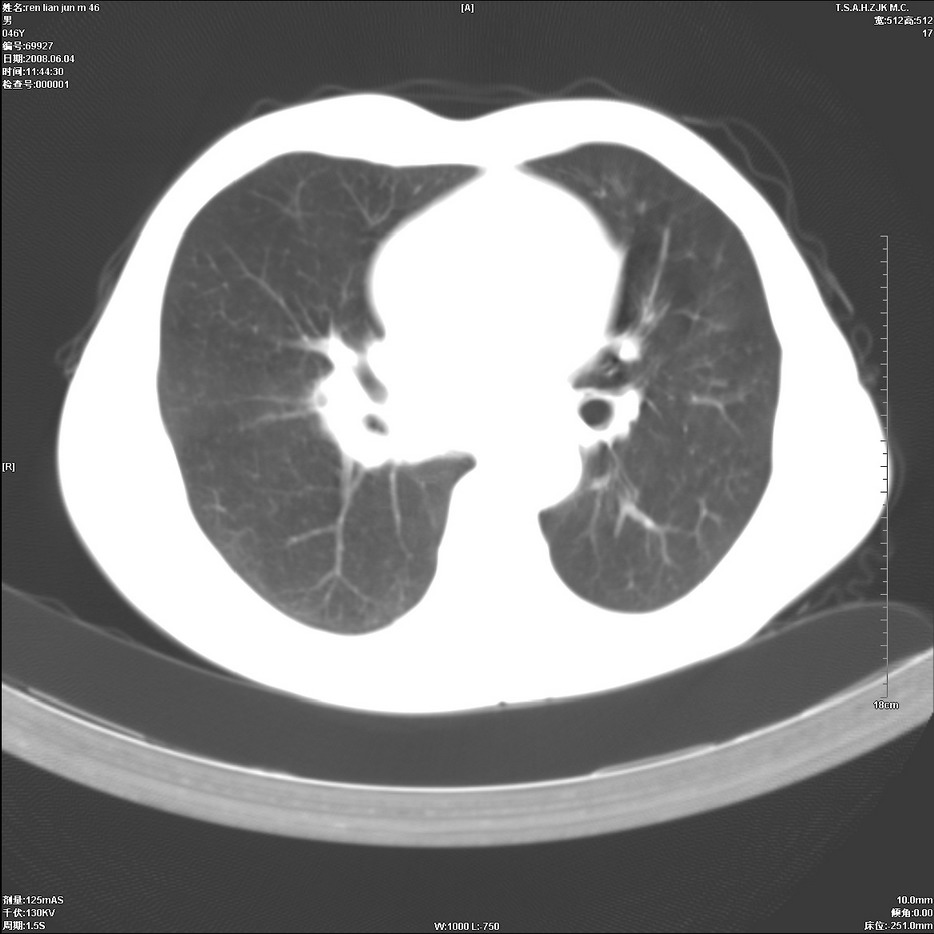

以下是引用qiu999在2008-6-5 17:14:00的发言:[br]考虑右肺中心型肺癌.颅内应做增强检查.

以下是引用形影不离在2008-6-5 19:18:00的发言:[br]右肺中心型肺癌并纵隔及左侧腋窝淋巴结转移,颅内应做增强检查。

以下是引用杀毒软件在2008-6-5 18:33:00的发言:[br]支持考虑右肺中心型肺癌,颅内病变是不是转移,不好说